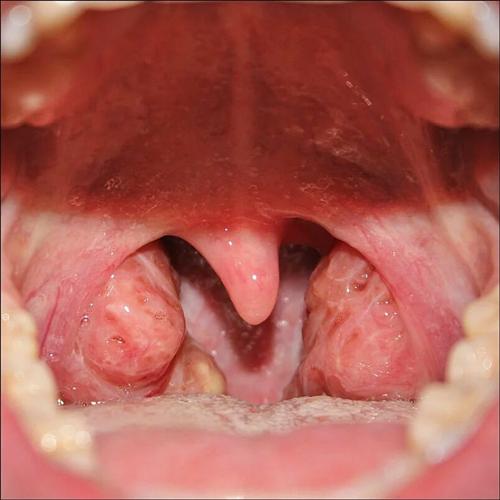

症状二:早期癌变时,患者的扁桃体,可能会有坚硬的凹凸不平的硬块产生,但是基本无痛感,不容易自己察觉到,后期这些硬块会慢慢的变得肿大,并且伴随着记忆的吞咽上下活动,可能会压迫到气管时,声音嘶哑。

症状三:扁桃体的硬块逐渐变大,不仅会使声音嘶哑,还会造成呼吸不畅,难以下咽,并且当颈静脉受到压力时,患者可能会出现面部水肿的情况,甚至发生肺转移和骨转移产生病理性骨折。